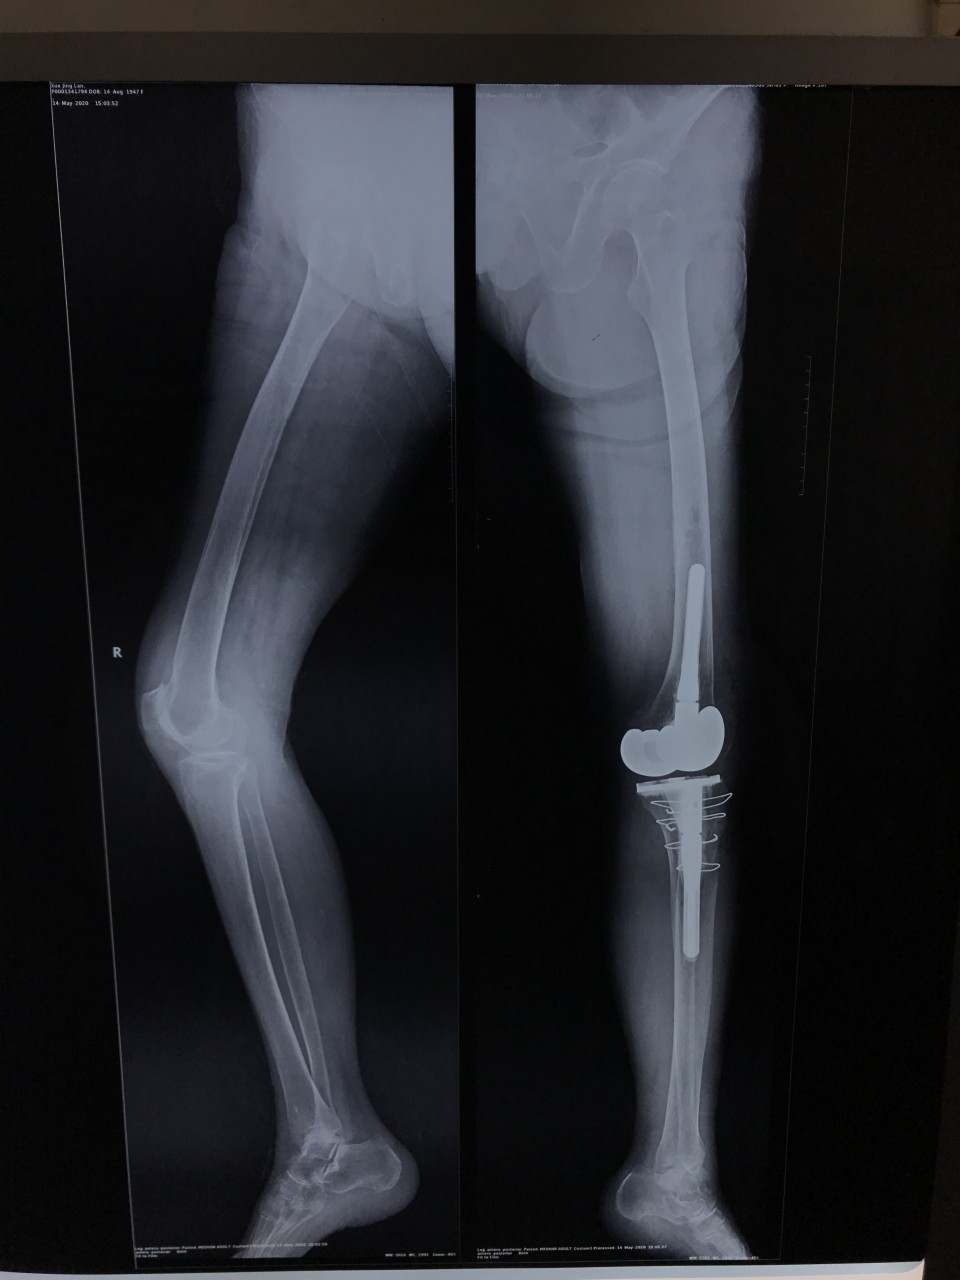

5月11日,一位72岁女性患者因“双膝关节疼痛伴活动受限8年,加重半年”入院,术前摄片提示双侧膝关节骨性关节炎。左侧膝关节伸直型僵直,屈伸活动度范围为0°。 我科胡孔足主任术前结合患者病史,体检及辅助检查,制定详实方案,先行左侧全膝关节置换术,术中采用TTO(胫骨结节截骨术),患者术后第二天下地正常行走,5月18日出院时已经能够完全自主抬腿,膝关节屈曲可达100°,减轻了患者的疼痛,明显提高了生活质量,疗效满意。

TTO通过截骨来达到远端松解的目的, 而不损伤与伸膝功能相关的软组织。这样在术后的修复过程中就是安全牢固的骨修复, 并且允许早期进行康复锻炼以尽快恢复股四头肌的功能,是一种安全可靠并且效果非常好的增加膝关节显露的方法,能够避免膝关节僵直造成胫骨结节撕脱骨折及髌韧带断裂等灾难性并发症。